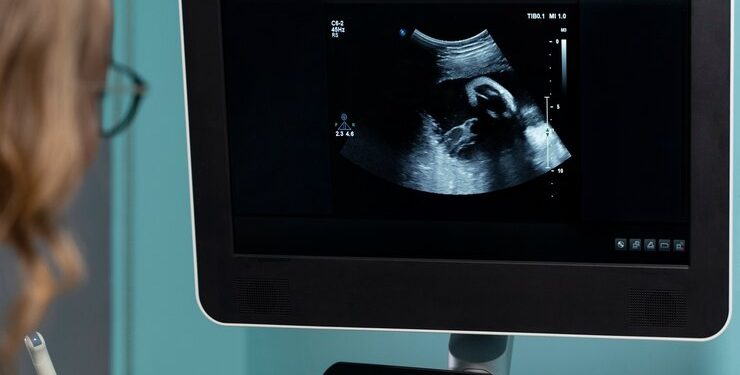

Сканер УЗИ Mindray MX7 широко применяется как в диагностике, так и в оперативном вмешательстве. Он является надежным помощником врачей различных специальностей, обеспечивая точные и качественные результаты исследований. Наиболее часто данный сканер используется при обследовании женщин в период беременности, поскольку он позволяет осуществлять ультразвуковой контроль развития плода, а также обнаруживать любые патологии или аномалии в структуре органов малыша.

Одним из ключевых направлений применения сканера УЗИ Mindray MX7 является акушерство и гинекология. С помощью этого устройства можно проводить всестороннюю оценку состояния матки, яичников, плода и плодных оболочек. Благодаря высокому разрешению изображения и режиму Doppler, врачи получают детальную информацию о кровотоке, что позволяет диагностировать различные патологии и контролировать развитие беременности.